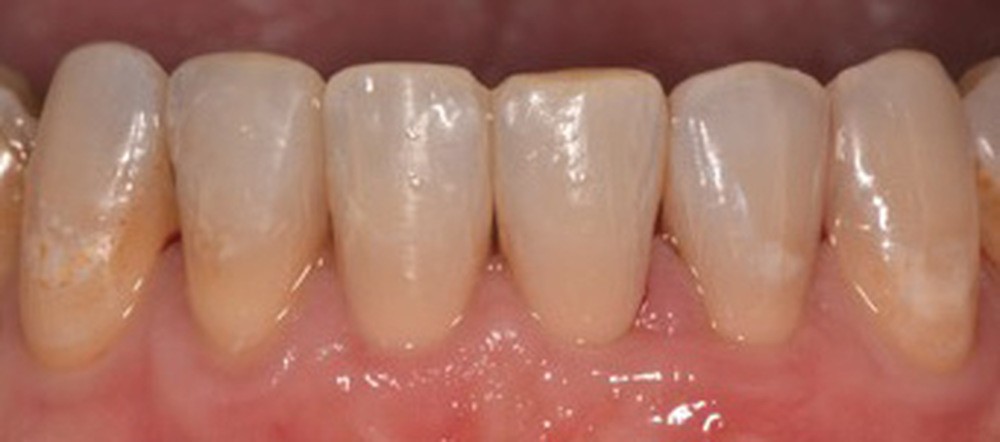

Le Pr Olivier Sorel insistera sur l’importance du respect des formes et des proportions anatomiques, pour éviter de voir apparaître, notamment chez les adultes, de très inesthétiques triangles noirs lors de la phase d’alignement (fig. 6a-b). Il présentera sa démarche diagnostique (évaluation de la forme des dents et de la dysharmonie dento-dentaire, fig. 7a-c) et l’intégration de la réduction amélaire proximale au plan de traitement, afin de s’assurer, en fin de traitement, la présence de papilles gingivales et donc d’un sourire harmonieux (fig. 8a-d).

Les Drs Marie Clément et Clara Marcoux aborderont ensuite les différents apports de la dentisterie esthétique aux traitements orthodontiques. Les problèmes de dyschromies isolées ou généralisées, congénitales ou acquises seront développés ainsi que les anomalies de proportions dentaires (dents riziformes…), le maquillage (transformation d’une canine en incisive latérale…) et le remplacement des dents antérieures. Les auteurs présenteront l’intérêt du Digital Smile Design dans le diagnostic et la communication et l’arsenal thérapeutique à notre disposition pour améliorer la satisfaction de nos patients (éclaircissement, traitement des taches de l’émail, composites stratifiés, fig. 9a-d).